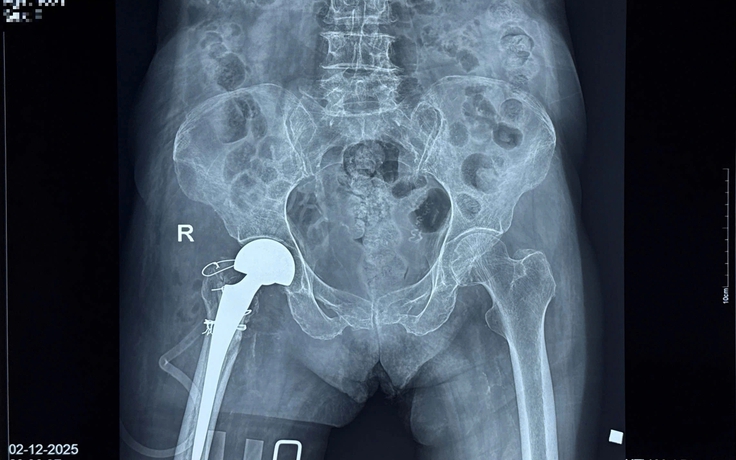

Thay khớp háng thành công cho cụ bà 100 tuổi

Cụ bà 100 tuổi bị tai nạn sinh hoạt tại nhà chấn thương nghiêm trọng đã được phẫu thuật thay khớp háng thành công tại Bệnh viện đa khoa Trà Vinh.